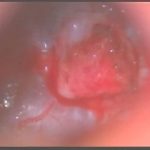

手術前1